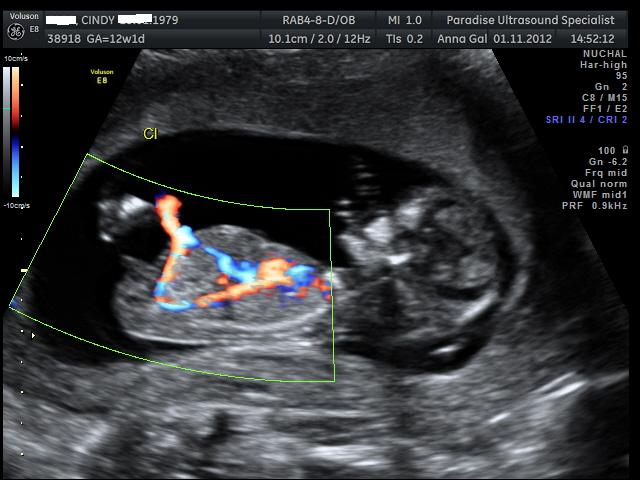

Here are the pics from my NT scan, the tech had a guess she said she is 70% positive the sex is.... can you guess? UPDATE - It's a boy :)